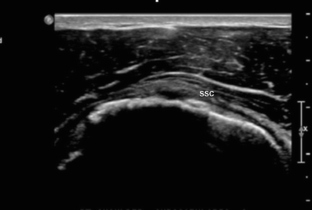

Fig. 1